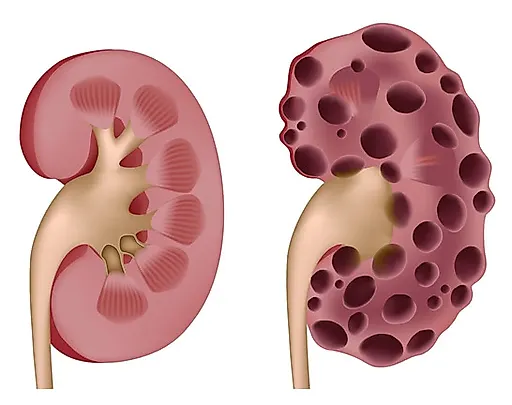

Мочевые органы и половые железы закладываются независимо друг от друга, но при дальнейшем развитии они формируют анатомически единую систему органов.Аномалии развития мочеполовых органов составляют более 30 % всех врожденных пороков развития.

Все аномалии развития почек создают условия для нарушения уродинамики, стаза мочи, инфицирования и развития тяжелых осложнений. Наиболее тяжелым осложнением у детей является пиелонефрит, при поздней диагностике которого развиваются деструктивные изменения в почке. Именно поэтому актуальными становятся ранняя диагностика и своевременная коррекция пороков развития органов мочеполовой системы.